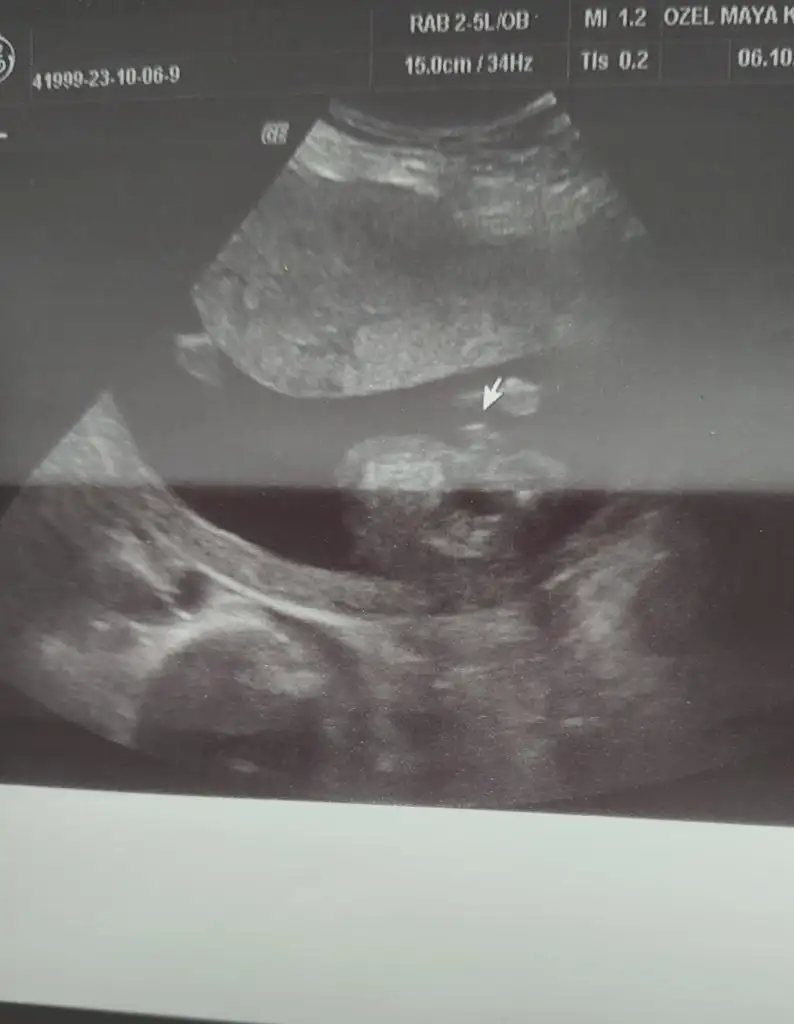

ErkkBakabilirmisiniz

ErkkEki Görüntüle 3313896 Bana da bakar mısınız 12+3